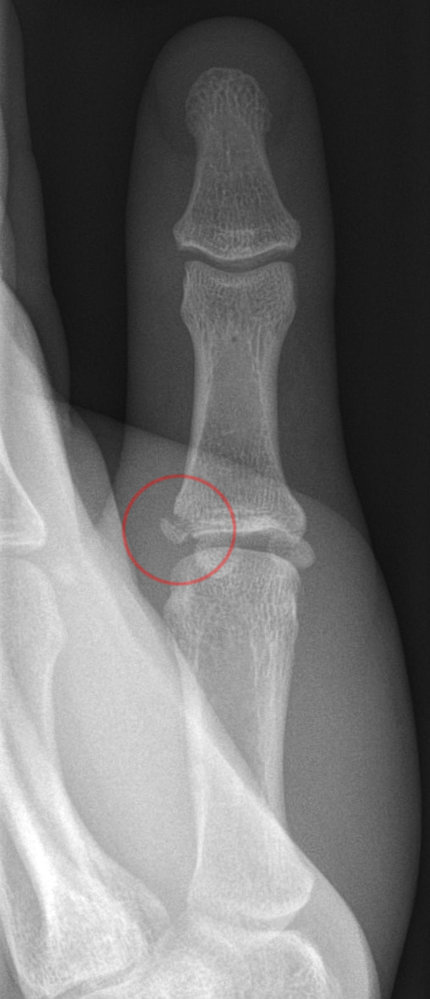

Skier’s thumb x-ray